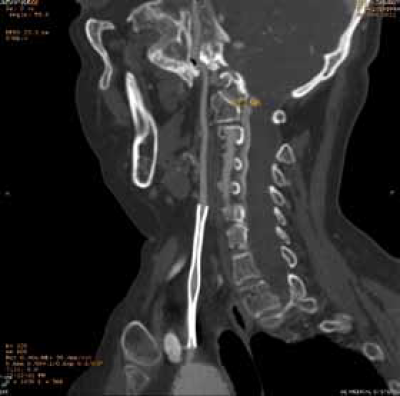

Nepotpuno ekspandirani stent u zajedničkoj karotidnoj arteriji.

Multislajs CT angiografija supraaortičnih grana – restenoza zajedničke i unutrašnje karotidne arterije (desno) nakon standardne endarterektomije,

posle 19 godina.